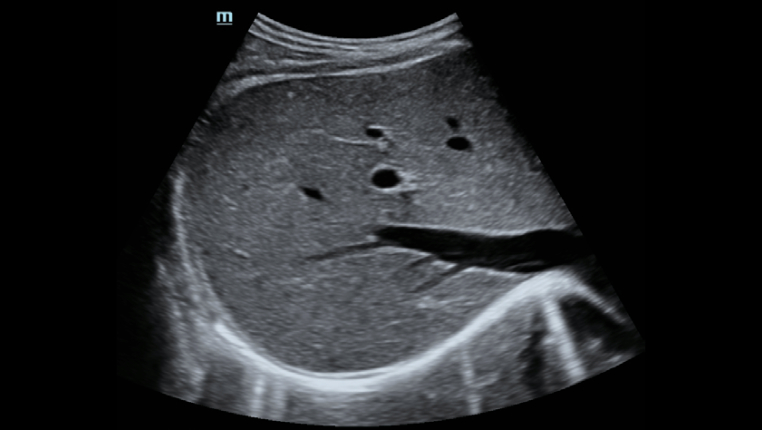

Zahlreiche Ultraschall-L?sungen*

┬и Professionelle Ultraschallsonde zur Erleichterung der Untersuchung von Aszites usw.

┬и Spezielle, ultraschallgesteuerte Punktion zur Erh?hung der Genauigkeit der Biopsie

┬и Exzellentes Ultraschallbild und ebensolche Ultraschallfunktion erm?glichen umfassende Bewertung von Lebermorphologie und H?modynamik.

┬и Spezielle, ultraschallgesteuerte Punktion zur Erh?hung der Genauigkeit der Biopsie

┬и Exzellentes Ultraschallbild und ebensolche Ultraschallfunktion erm?glichen umfassende Bewertung von Lebermorphologie und H?modynamik.